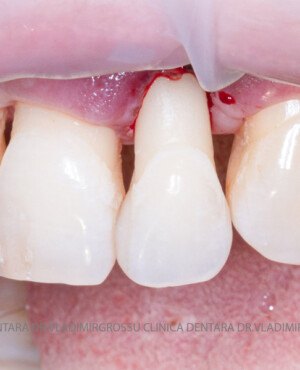

Adiția de gingie (gingivoplastia)

Aditia gingivală este o procedură chirurgicală ce corectează diverse probleme estetice și funcționale, cum ar fi recesiunea gingivală. În implantologia modernă, aditia de țesut moale este utilizată aproape în fiecare intervenție de inserție a implantului dentar pentru a asigura un aspect estetic natural și o bună integrare a implantului în cavitatea bucală.